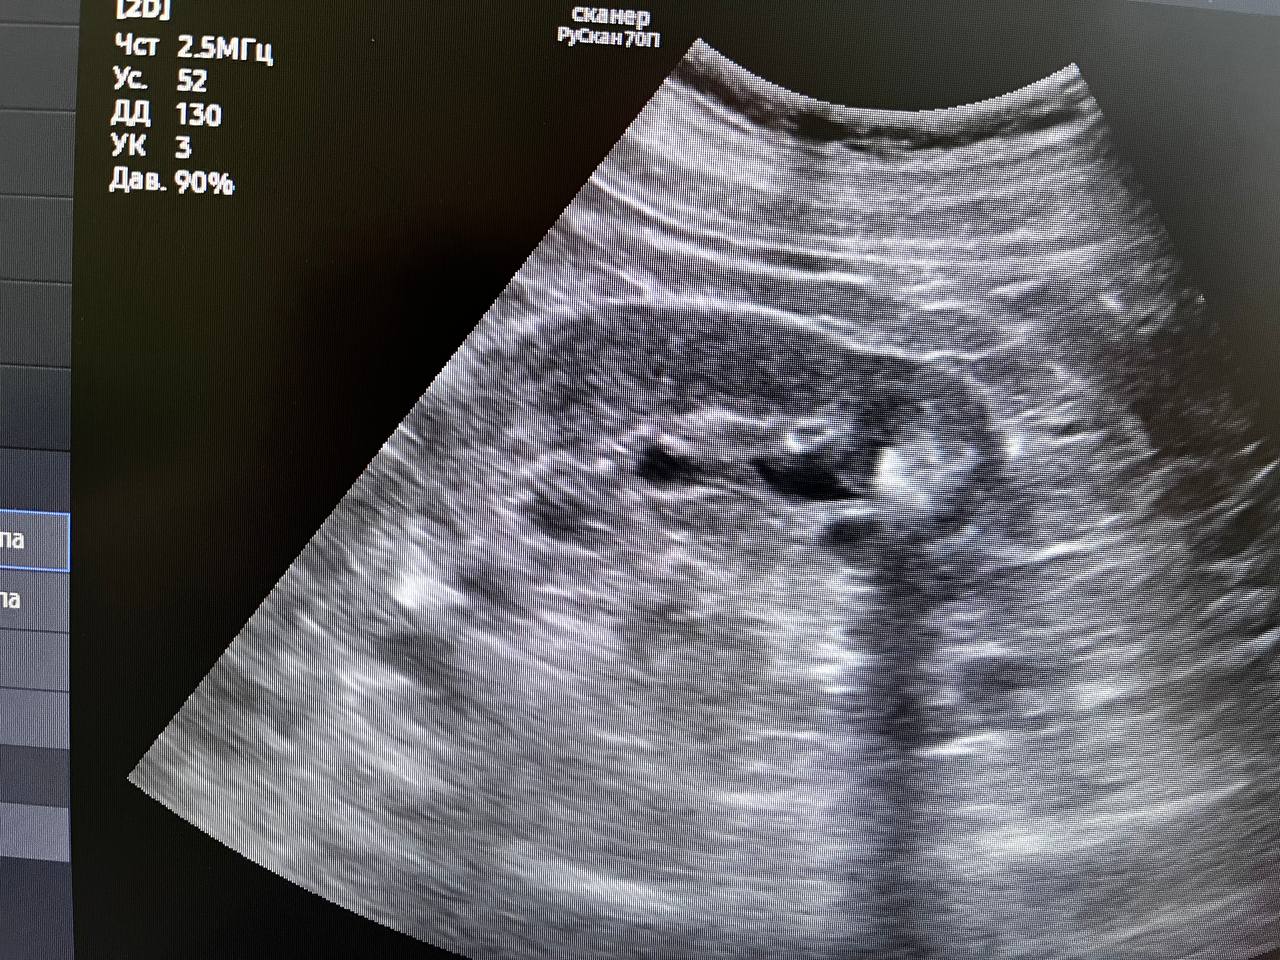

В минувшую субботу в день здоровой почки проверить своё здоровье пришли 22 человека. У двоих из них выявлены серьёзные патологии при полном отсутствии жалоб. Остальные пациенты были с мелкими кистами почек до 10мм и "песочком". Всем выполнено УЗИ, выданы направления на лабораторные обследования. Так же были пациенты без патологии, пришедшие для комплексного обследования со стороны мочевыделительной системы, выполнено УЗИ, выданы направления на общий анализ мочи "У одного пациента - мочекаменная болезнь, чашечные камни с обеих сторон до 15мм. Направлен на МСКТ для установления точной локализации и положения камней с целью подготовки для плановой госпитализации и оперативного лечения. У второго пациента выявлено образование в правой почке до 12мм. Пациент направлен на МСКТ для верификации", - уточнил врач-уролог поликлиники для взрослых обособленного подразделения им. М.В. Гольца Щёлковской больницы в г. Фрязино Владимир Орленко Щёлковская больница проводит тематические дни открытых дверей на регулярной основе, благодаря чему жители городских округов могут проверить своё здоровье без ожидания свободной записи к узким специалистам. |